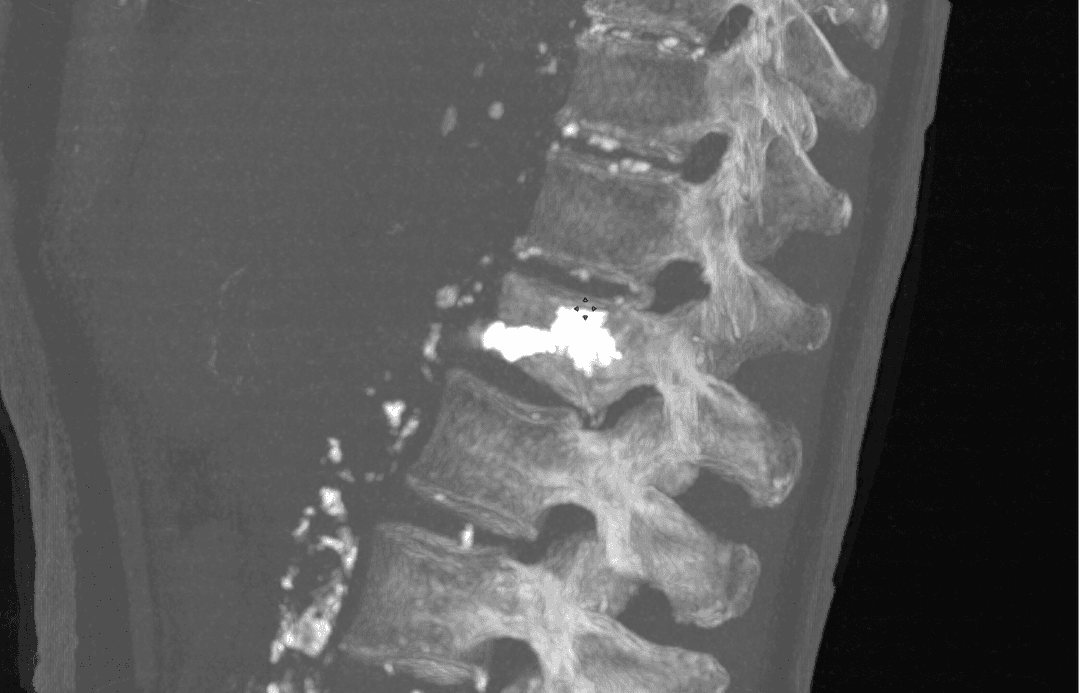

Résultat après injection de ciment

Injection du ciment

Une fois l’aiguille positionnée correctement, le ciment acrylique est injecté de façon contrôlée. Cette étape cruciale, suivie en continu grâce aux images, garantit une distribution homogène du ciment tout en minimisant le risque de fuite hors du vertèbre.